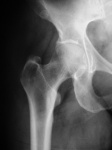

От хирурга.

p5280146.jpgp5280148.jpgp5280149.jpg